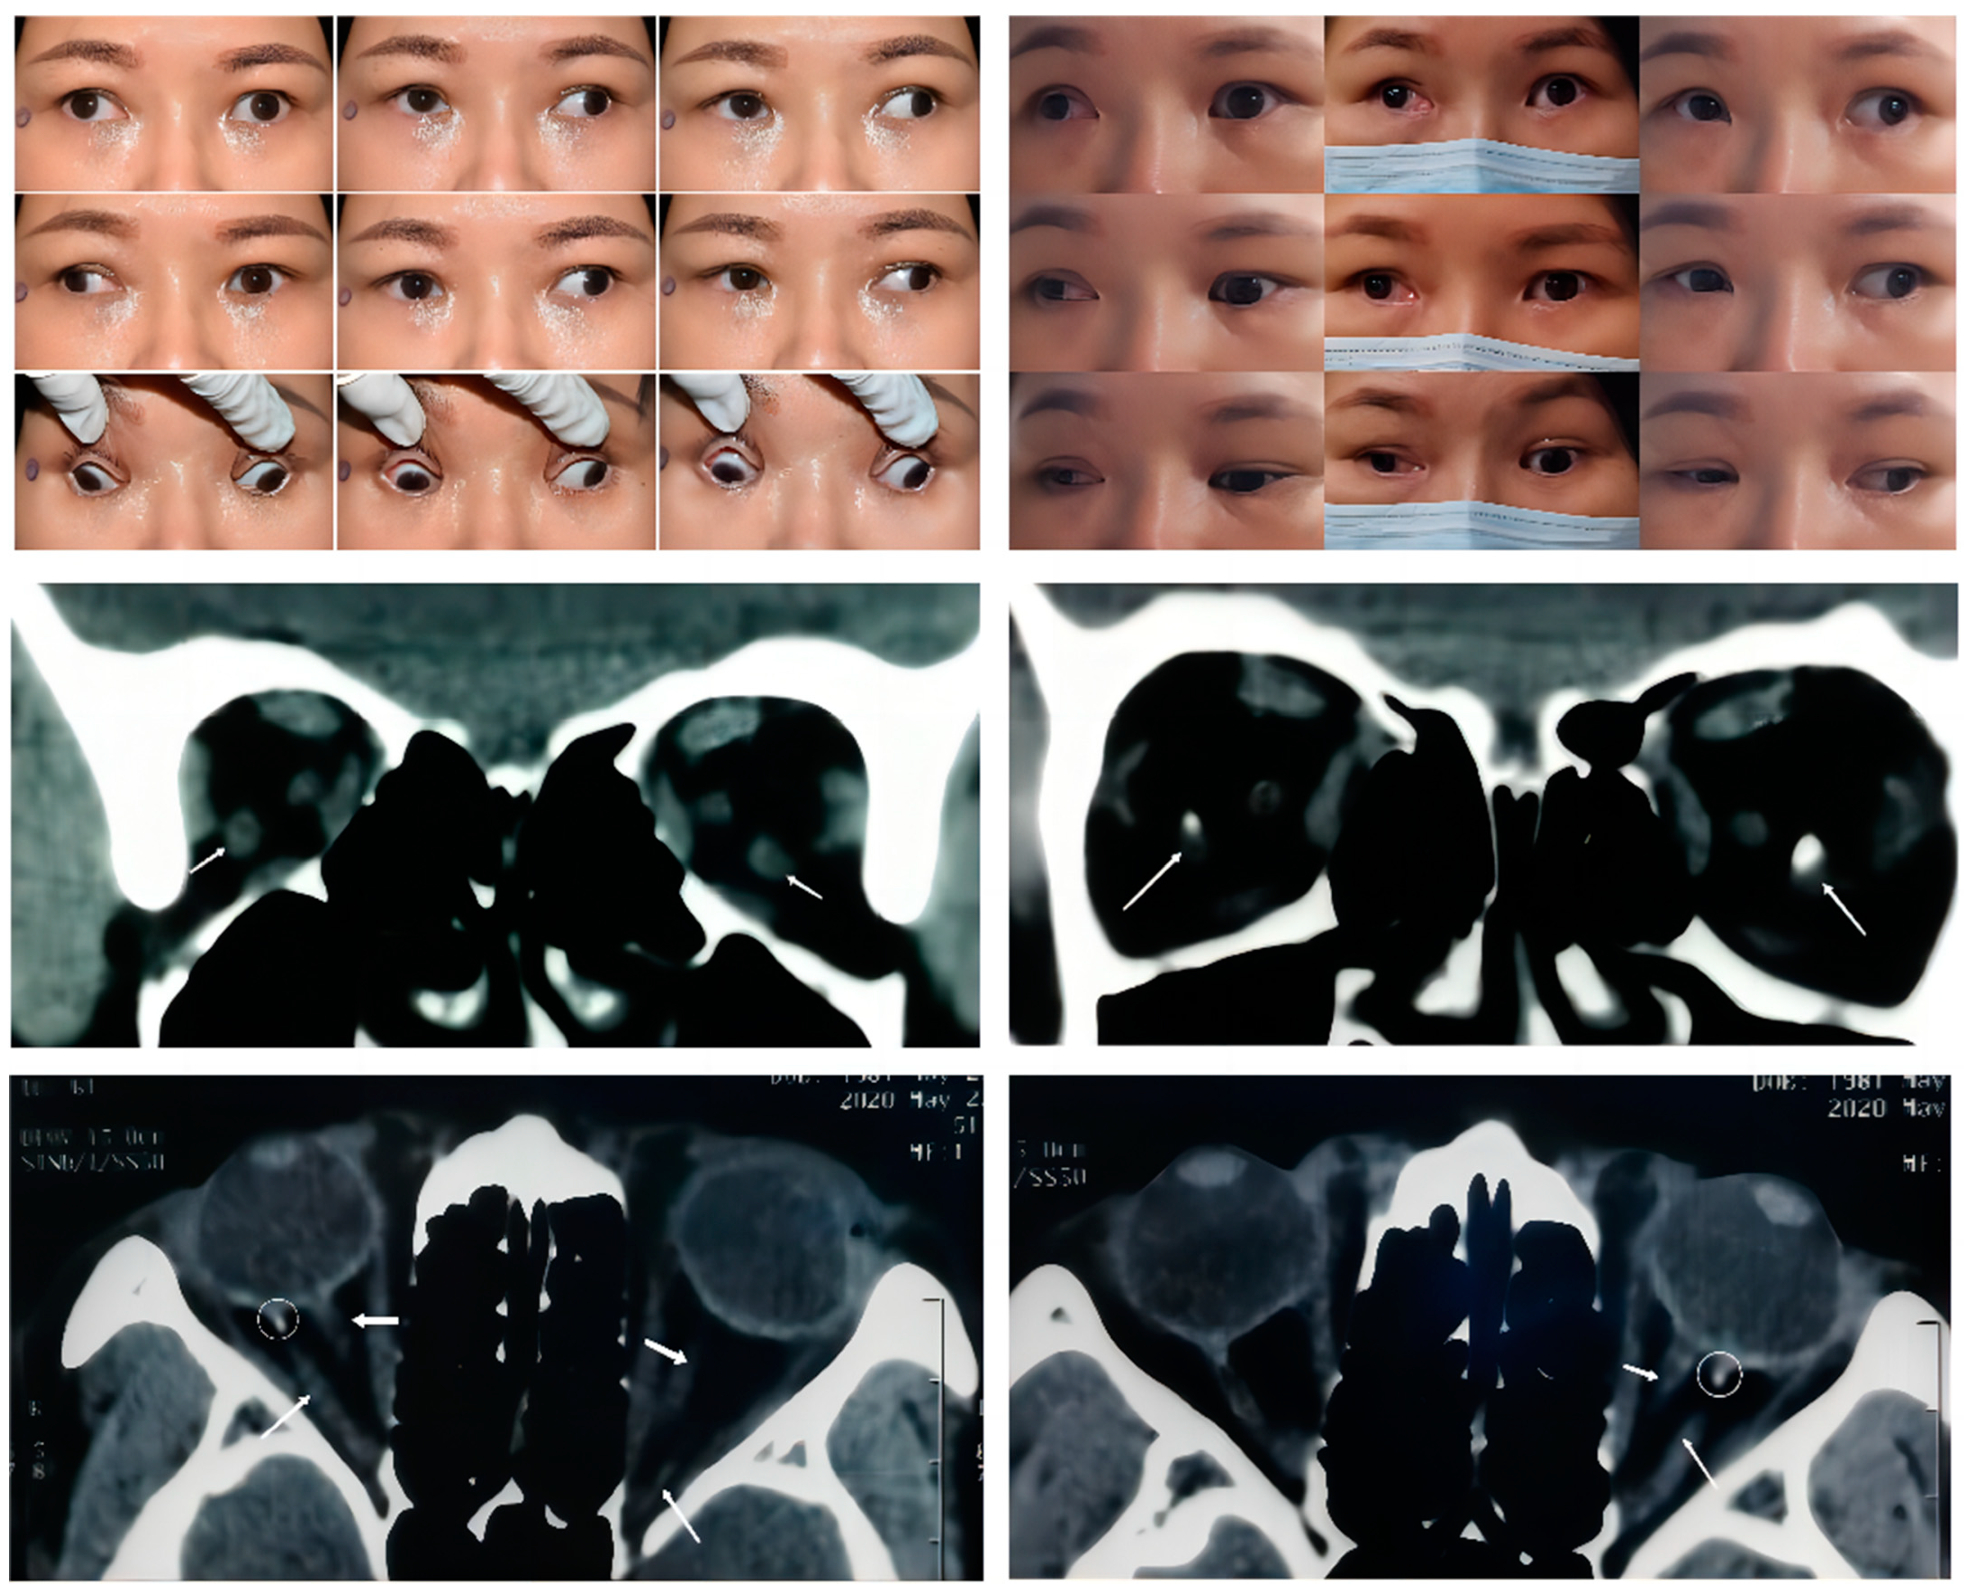

Figure 1. Upper panel: Nine gaze photographs of Case 1 showing a preoperative 65 PD alternating exotropia and a large A pattern strabismus. A moderate bilateral limitation of adduction and supraduction and mild bilateral limitation of infraduction were present in this case (left). Sixteen months after a second strabismus surgery (right), there was a slight improvement in the adduction of the right eye. A residual 25 PD exotropia and large A pattern strabismus remained. Middle Panel: Arrow in the coronal CT scan indicates a bilateral symmetric accessory extraocular muscle. The high-density image within the muscle suggests a local calcification just behind the posterior pole of the eyeball (the right picture). Bottom Panel: Thin arrow in the axial CT scan indicates that the accessory extraocular muscle in both eyes originat from the apex of the orbit and inserting into the posterior globe lies between the lateral rectus and optic nerve. Thick arrow: the optic nerve. Circle: local calcification within the muscle.

In this study, we distinguished four types of SEOM within the 12 cases reviewed. These categories were based on the origins and insertions as observed from the imaging results. Type 1 SEOM involves a discrete accessory EOM inserting into the sclera, which is well-defined and tends to be readily identified with imaging. Therefore, there have been many reports describing this type of SEOM. Type 1 SEOM tends to insert into the posterior globe beneath the optic nerve, especially the inferotemporal quadrant [4,5,7,12]. Valmaggia [5] reported on the case of a 6-year-old boy with a similar anomaly and elevation deficiency in the left eye but no subjective complaints; thus, no strabismus surgery was performed. A case mentioned by Dobbs et al. [4] was diagnosed as Duane syndrome, and the patient underwent lateral rectus recession at the age of 23 months. Then the remaining limited supraduction and globe retraction indicated the existence of SEOM. The CT scan identified bilateral tissue isodense to muscle that was inferolateral to the optic nerve, and the postoperative pathological examination suggested that the tissue nature was similar to a normal EOM. Case 1 (Figure 1) displayed continuous exotropia after a previous strabismus surgery performed elsewhere (details unknown). We observed a 65 PD exotropia and 5 PD right hypertropia in the primary gaze with a moderate limitation of bilateral adduction and supraduction as well as a mild limitation of bilateral infraduciton in adduction. Coronal and axial CT scans revealed a bilateral symmetric accessory muscular tissue coursing from the annulus of Zinn to insert into the inferolateral sclera posteriorly. Interestingly, there was muscular calcification proximal to the globe in Case 1, a finding which has not been reported in previous studies. Compared with the other case types in this study, the clear structure of the SEOM in type 1 showed a smaller correlation with the optic nerve, indicating that it had less impact on visual acuity.